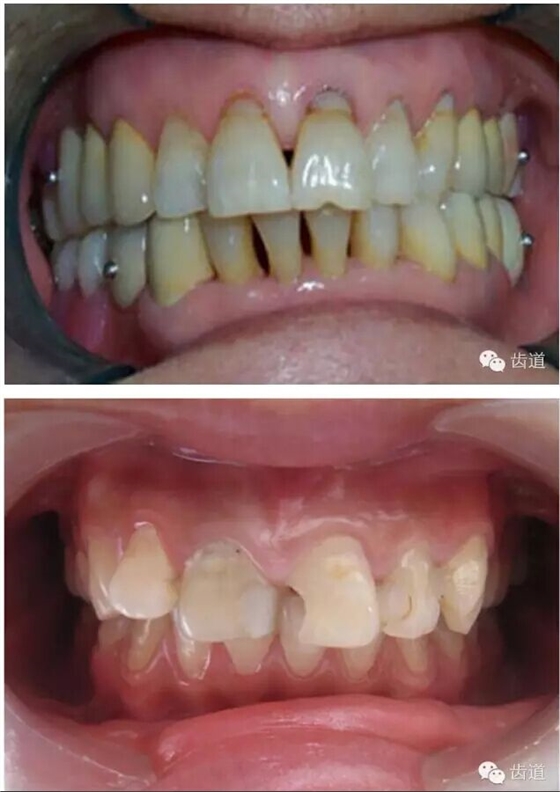

l保護(hù)牙體組織

l基牙具有良好的固位形

l基牙具有良好的抗力形

l預(yù)留修復(fù)體的空間

l邊緣的適合性

l保護(hù)牙周組織

l多個(gè)基牙時(shí)就位道的調(diào)節(jié)